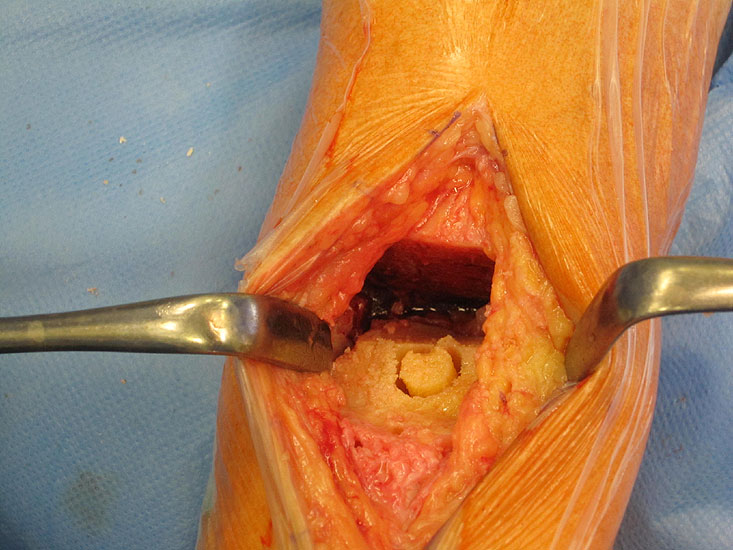

• Prothesenplanung anhand von Röntgenschablonen (Abb. 1 und 2).

• Die Fersen des Patienten sollen mit dem Tischende abschließen (Abb. 3)